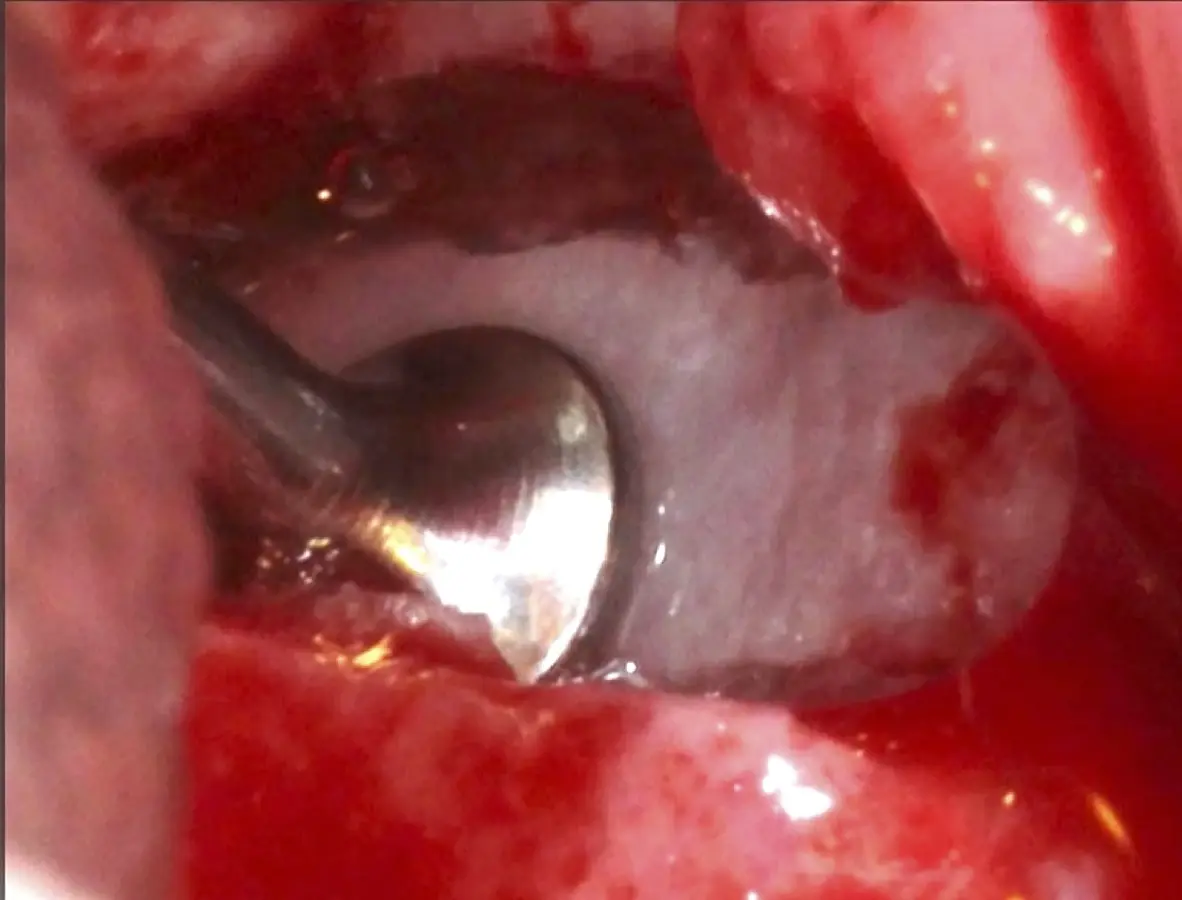

Figura 17. Inicio del desprendimiento de la membrana de Schneider con el inserto de presión hidráulica.

Figura 25. Introducción del bloque óseo de la pared lateral dentro del seno maxilar: inicio del desprendimiento de la membrana con el inserto de presión hidráulica.